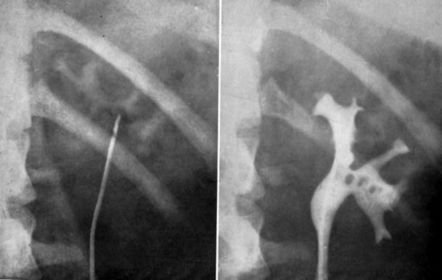

Bifid System Double collecting system Can appear: double renal pelvis or ureter in one or both kidneys (upper ureter may insert into bladder below trigone, outside bladder in urethra, or seminal vesicles), or double kidney Can cause: obstruction in upper pole collecting system or reflux in the kidney